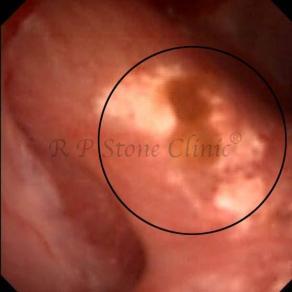

Kidney stone is a solid mass of CRYSTALS. It is the process of crystallization which initiates the formation of kidney stones. This happens in nephrons or units of kidney. Once a small crystal is formed, it can both grow & unite with other crystals leading to the formation of small concretion which eventually forms a stone. Once these large crystals detach from the collecting ducts, the process of stone formation starts in the renal collecting system. A recurrent kidney stone former is advised to know a little bit about something known as Randall’s plaque. Alexander Randall discovered plaques on the renal papillae eight decades back based on examination of 1154 pairs of autopsied Kidneys. He described these renal papillary lesions as cream colored or milk patch areas composed of calcium phosphate & calcium carbonate. These plaques could act as NIDUS for formation of KIDNEY STONE. Calcium Oxalate stone can form on this nidus & then detaches from this plaque to become a free floating stone in the collecting system of kidney

These images are taken as snap shots from the video recording of RIRS Surgery done at our hospital. These are Randall’s Plaques seen with Digital FLEX XC & Digital FLEX XC S. The cream or whitish patches are seen on the tips of RENAL PAPILLAE as seen in images below.

Randall’s Plaques may lead to the formation of Stones.

Those kidney stone patients who have Randall’s Plaques in their kidneys are more likely to form stones again (Recurrent Stones).

Stone Patients in whom Randall’s Plaques are detected at the time of RIRS Surgery should undergo regular ultrasound examination for early detection of stones.

Patients of Stones with Randall’s Plaques in their Kidneys should drink plenty of fluids in addition to Orange Juice & Lemonade.